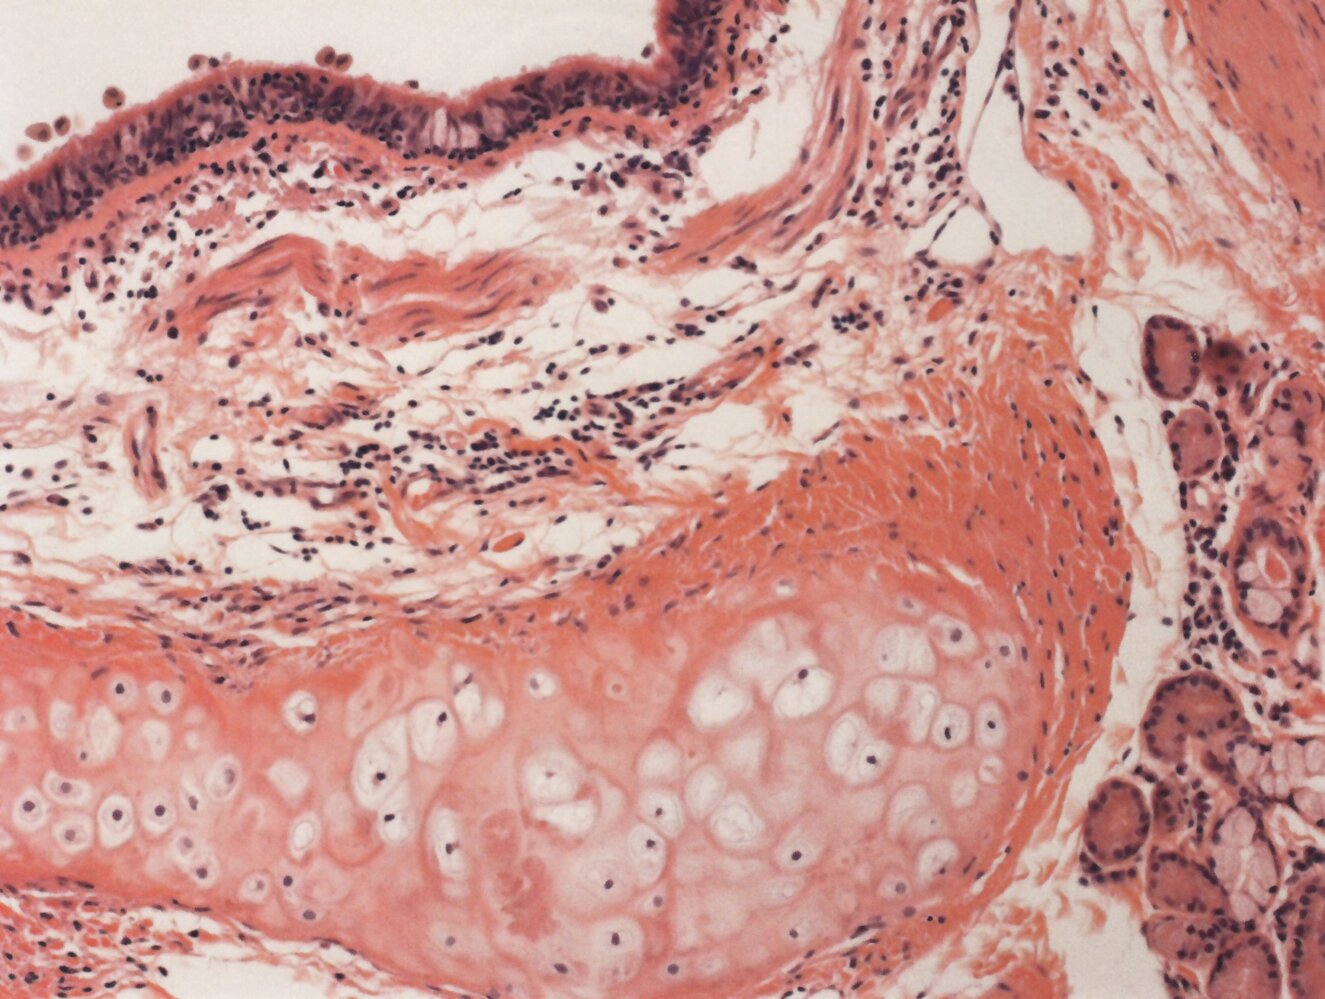

• Trachea and bronchi

• Pseudostratified ciliated columnar epithelium: important for mucociliary clearance

• Goblet cells

• Cartilage: C-shapedhyaline cartilage rings in the trachea and hyaline cartilage plates in the bronchi provide structural support.

• Annular ligaments of trachea: horizontal fibrous bands that join the tracheal cartilage rings together

• Smooth muscle

• Seromucous glands (secrete mucus)

• Basal cells